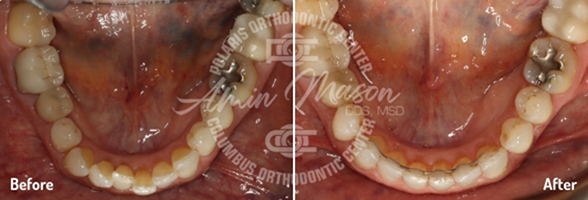

Case 7

An adult male patient presented to our office with a deep bite, crowding, and tooth wear. The patient exhibited class II molar occlusion, severe deep bite, and maxillary/mandibular crowding. The patient was treated with class II corrector and limited maxillary braces for a short time and was transitioned to Invisalign clear aligners. Patient achieved fantastic results and was very satisfied with the results. Treatment time: 22 months.